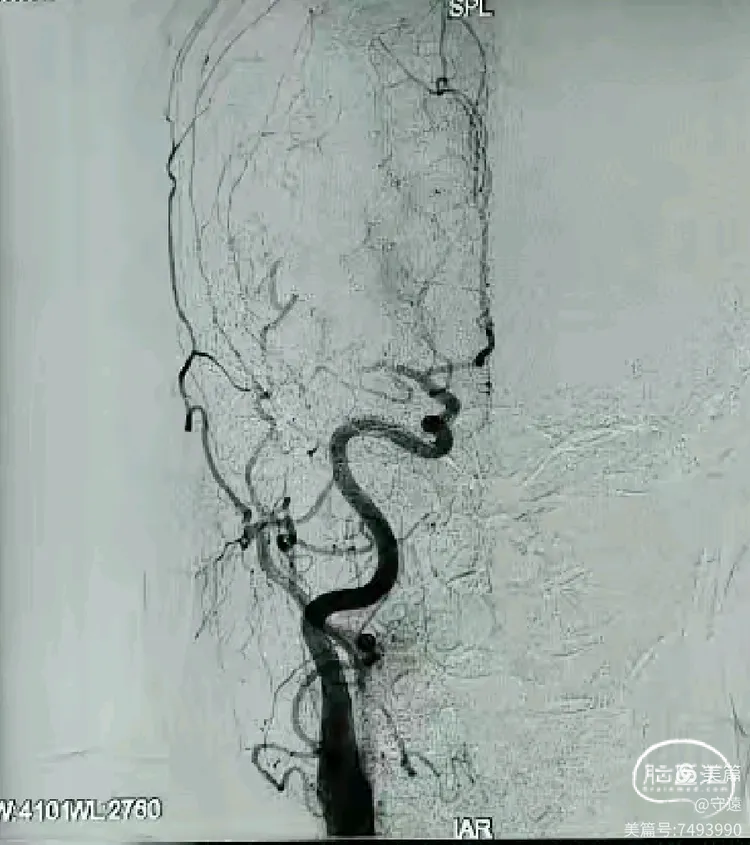

局麻下行血管内治疗:行右侧股动脉穿刺,脑血管造影真实左侧大脑中动脉M1段闭塞。血管断面呈“刀切征”or“截断征”。大脑前动脉部分代偿。

手术过程:银蛇070中间导管到达M1段直接抽吸。

裸奔:由于颈内血管路途迂曲不明显,路图下银蛇070中间导管“裸奔”到达M1段接触血栓部位。

踹马桶抽吸: “猛抽”将血栓吸入导管,进行快速踹、踹、踹马桶,注射器无回血,边踹负压抽吸,撤出体外,检查中间导管和注射器抽出2块红色血栓,冒烟观察血管再通。

抗血小板聚集:再次将微导管置于M1段起始部,给予替罗非班8mL,1mL/min推注。造影显示远端血流通畅。